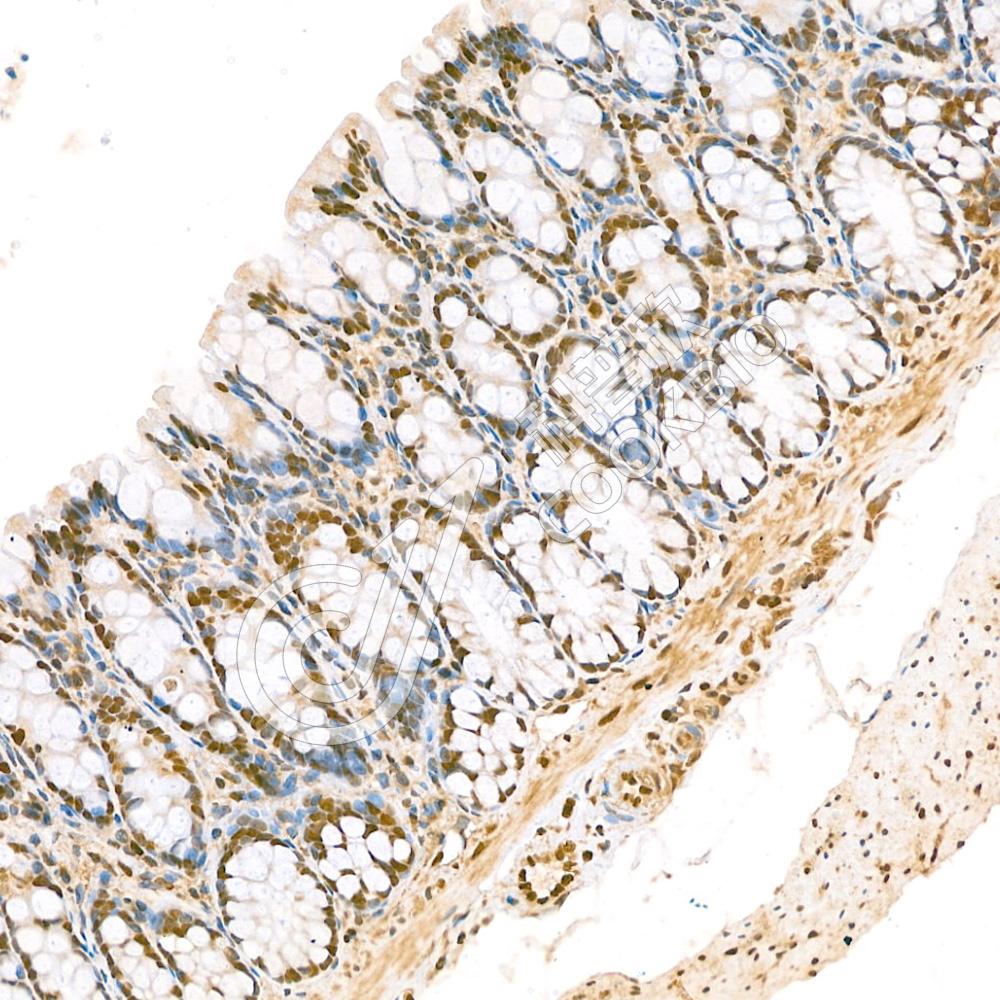

Anti-Glucagon 兔多克隆抗体

兔多抗

糖代谢,激素及受体

应用

|

种属

:

IHC/IF

H,M,R

货号:K133291-100

规格:100 μL

¥ 1900